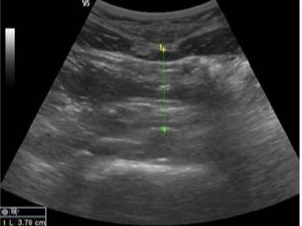

신장 및 요로계 질환

- 신장결석: 콩팥 내 결석 확인 가능

- 수신증: 요관 폐쇄 등으로 신장이 부어 있는 상태 확인

- 신장 종양, 낭종: 악성·양성 종양 여부 1차 판별